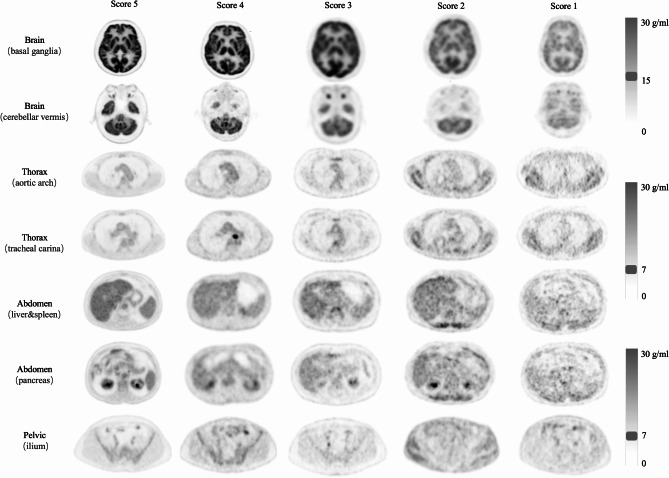

Methods: This retrospective multicenter study included clinical whole-body [18F]FDG PET/CT scans from 718 patients. Automated identification and localization algorithms were applied to select predefined pairs of PET and CT slices from whole-body images. Fifteen experienced experts, trained to conduct blinded slice-level subjective assessments, provided average visual scores as reference standards. Using the MANIQA framework, the developed IQA model integrates the Vision Transformer, Transposed Attention, and Scale Swin Transformer Blocks to categorize PET and CT images into five quality classes. The model's correlation, consistency, and accuracy with expert evaluations on both PET and CT test sets were statistically analysed to assess the system's IQA performance. Additionally, the model's ability to distinguish high-quality images was evaluated using receiver operating characteristic (ROC) curves.

Results: The IQA model demonstrated high accuracy in predicting image quality categories and showed strong concordance with expert evaluations of PET/CT image quality. In predicting slice-level image quality across all body regions, the model achieved an average accuracy of 0.832 for PET and 0.902 for CT. The model's scores showed substantial agreement with expert assessments, achieving average Spearman coefficients (ρ) of 0.891 for PET and 0.624 for CT, while the average Intraclass Correlation Coefficient (ICC) reached 0.953 for PET and 0.92 for CT. The PET IQA model demonstrated strong discriminative performance, achieving an area under the curve (AUC) of ≥ 0.88 for both the thoracic and abdominal regions.